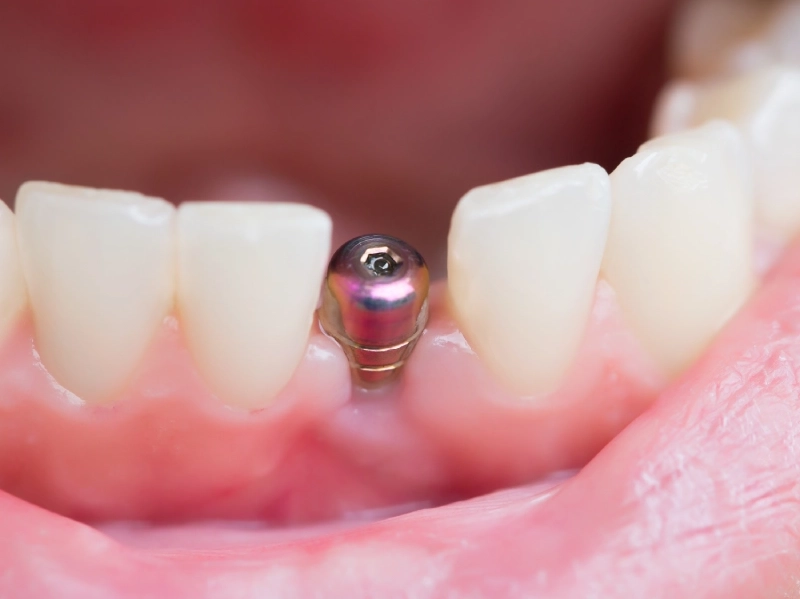

Với thiết kế đặc biệt cùng công nghệ xử lý bề mặt SA, Tekka thích hợp cấy ghép ở mọi trường hợp mất răng từ đơn lẻ đến toàn hàm, hơn nữa còn đạt thẩm mỹ tối ưu khi cấy ghép răng cửa.

Nhờ kết nối côn thuôn In-Kone® UNIVERSAL độc quyền không có ở bất kỳ loại Implant nào, Tekka có thể đặt âm 2mm dưới xương vỏ, vừa đảm bảo ổn định trong xương hàm, vừa mang tính thẩm mỹ cao sau khi phục hình.